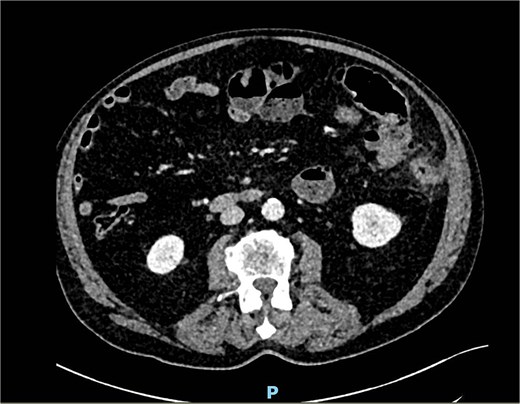

A performed CT scan showed a suspicious process in the left hemiabdomen with the involvement of the small bowel and its mesentery (Fig. 7), as well as enlarged lymph nodes. Therefore a radiological suspicion of malignancy was postulated. Adding to that a mechanical small bowel obstruction was seen in the CT scan due to the described mass.

An antibiotic therapy with piperacillin/tazobactam was empirically initiated as well as a conservative therapy of small bowel obstruction with oral intake of Telebrix®. We also scheduled further investigations ruling out a malignancy. The performed magnetic resonance imaging (MRI) of the abdomen then showed a jejunal diverticulitis (Fig. 8). During the hospital stay we observed a significant decrease of the inflammatory markers, a return of bowel movement with established stool passing as well as a pain-free patient. The antibiotic therapy was discontinued on the day of dismissal, on day 7.

MRI showing multiple jejunal diverticula on the mesenteric side.